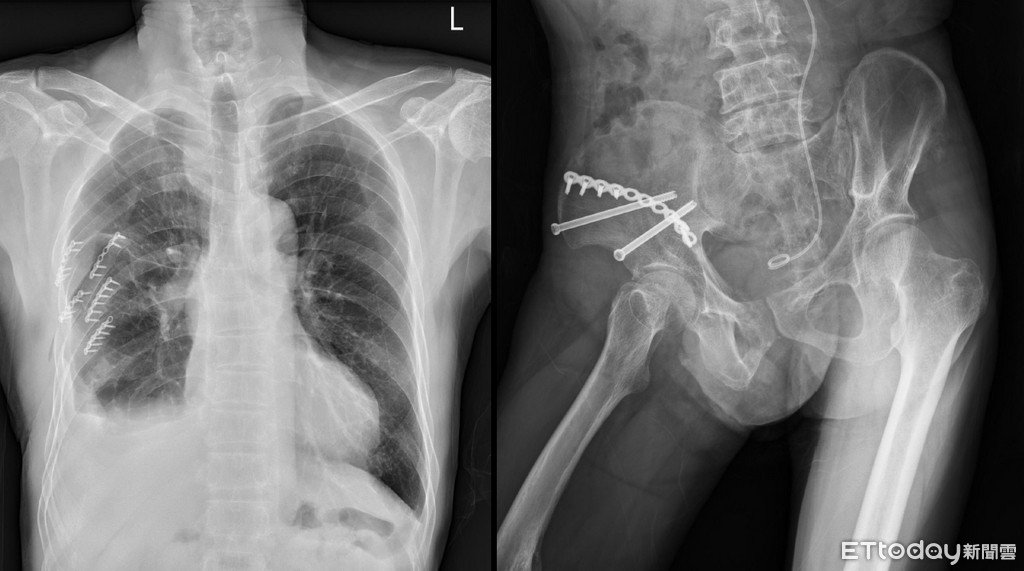

▲針對多重肋骨骨折患者,亦積極以手術固定,有效減輕疼痛,改善患者呼吸,早日脫離呼吸器並回復日常生活。(圖/成醫提供)

多重肋骨骨折也是重大外傷患者常見的問題,傳統治療為給予止痛藥物,若呼吸衰竭則以呼吸器長期維持;顏亦廷醫師說,近年來成大醫院外傷科嘗試手術介入治療,以胸腔鏡輔助之微創方式,引流血胸,固定肋骨骨折,有效止痛並改善呼吸功能。2010年以來,共幫助54患者完成肋骨骨折固定復位手術,術前使用呼吸器患者可約於術後2天拔管,術後約5天轉出加護病房。